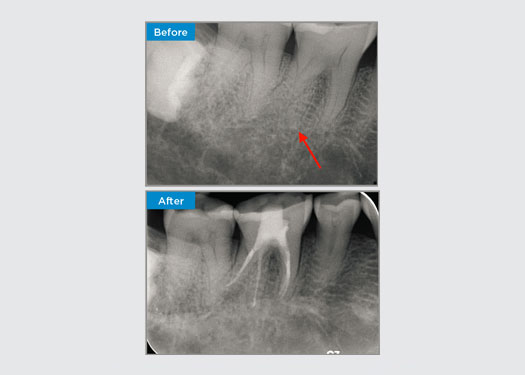

Casos clínicos

Los médicos de todas partes de Australia y Nueva Zelanda comparten amablemente presentaciones relevantes, interesantes y, a veces, desafiantes para los pacientes, junto con su selección de materiales y métodos para optimizar los resultados de sus pacientes.